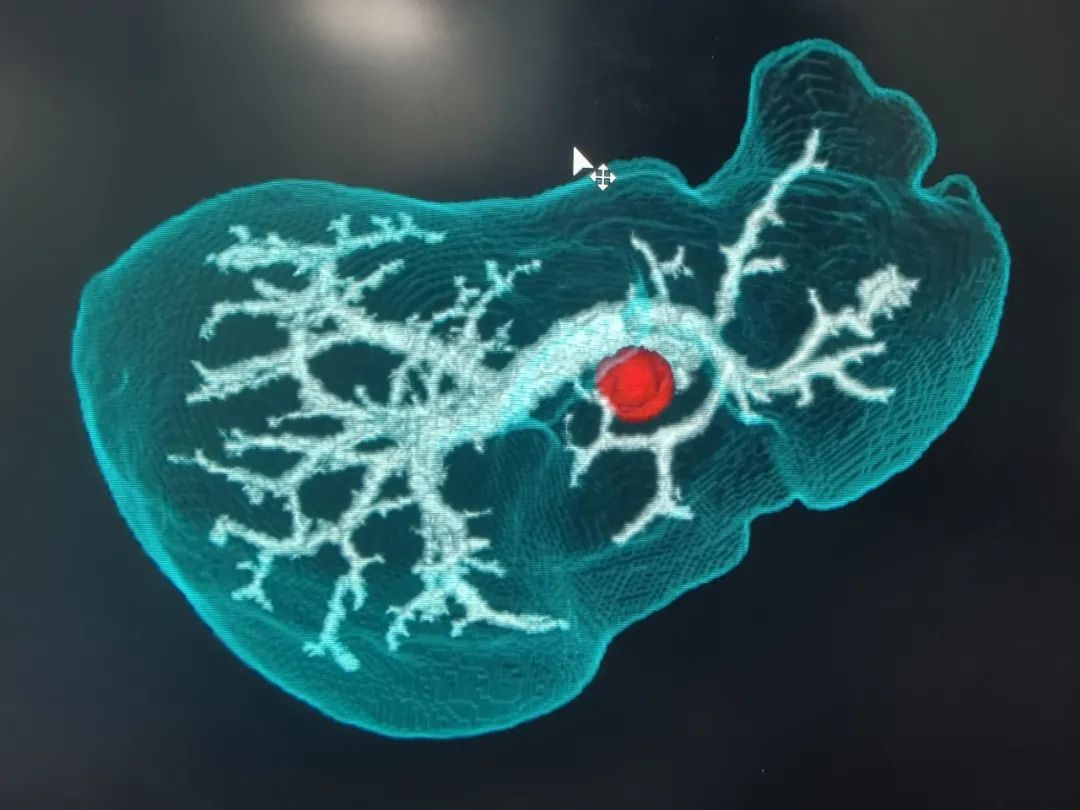

经过详细的体格检查,完善影像和实验室检查后,诊断其为:肝门胆管恶性肿瘤。普外科主任代坤介绍,肝门部胆管癌,就是长在肝门部胆管粘膜上皮的恶性肿瘤,因为位置特殊,起病隐匿,可能与胆管慢性炎症、胆管结石等有关。长期胆管炎会让胆管粘膜反复受损修复,胆管粘膜增生,可能发展成癌;有先天性胆管囊性扩张症、原发性硬化性胆管炎的人群,患癌的几率更高。值得警惕的是,患者早期症状可能不明显,随着肿瘤的生长,胆管被堵住,胆汁排不出去,黄疸会特别突出,出现皮肤、巩膜黄染,患者可能会有右上腹隐痛、胀痛,因为肿瘤影响消化,患者营养吸收不好消耗较大,会有吃不下饭、消瘦、没力气的表现。

基于术前影像,结合肿瘤实际累及程度、解剖变异以及切离极限点,外科团队邀请多科室开展MDT讨论,规划个体化精准手术方案。充分术前准备后,为其行“肝门部胆管癌根治术”。主刀手沉着冷静,仔细探查,精准分离,清扫组织,以雷霆之势完整切除病灶。“清点器械纱布,确认无误,关腹。”手术顺利,经过术后严格管理和精心护理,宗师傅很快康复出院,对东方医院集团广济医院普外科团队精湛的技术赞不绝口。